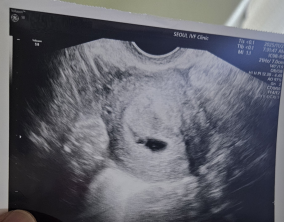

인공수정 1차의 기적